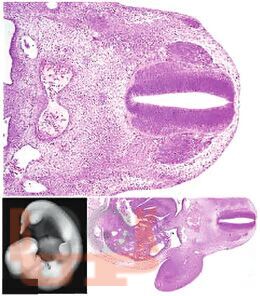

Практическое руководство посвящено клинической морфологии печени. Подробно представлены диагностические критерии поражений печени различной этиологии (инфекционные, метаболические, аутоиммунные, токсические, алкогольные, опухолевые и редкие формы). Ключевая особенность — комплексный подход с одновременным использованием световой и электронной микроскопии, а также схематических рисунков, дублирующих гистологические снимки. Большой объем иллюстративного материала (биоптаты, секционный материал) сопровождается морфологическими заключениями. Издание ориентировано на практикующих врачей разных специальностей и студентов старших курсов.